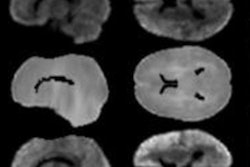

As part of the project, all participants received resting-state fMRI scans on a 3-tesla system (Magnetom Skyra, Siemens Healthineers) and self-reported their depression issues and sleep quality patterns. The fMRI data were then used to segment gray matter of the whole brain into 250 regions of interest for more detailed evaluation.

Cheng and colleagues discovered 162 functional connections involving areas associated with sleep. The key regions included the precuneus, anterior cingulate cortex, and lateral orbitofrontal cortex. Of those connections, 39 areas also were associated with the Depressive Problems scores.

Most important, the researchers found 11 brain areas with increased functional connectivity associated with both sleep and depression: the lateral orbitofrontal cortex, dorsolateral prefrontal cortex, anterior and posterior cingulate cortices, insula, parahippocampal gyrus, hippocampus, amygdala, temporal cortex, and precuneus.